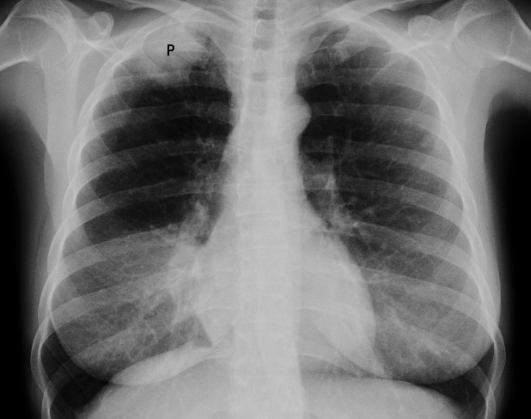

Chest X-Ray!!!!

• Focal lesion

• Pleural effusion

• Widened mediastinum due to enlarged hilar lymph nodes

• Diaphragm collapse